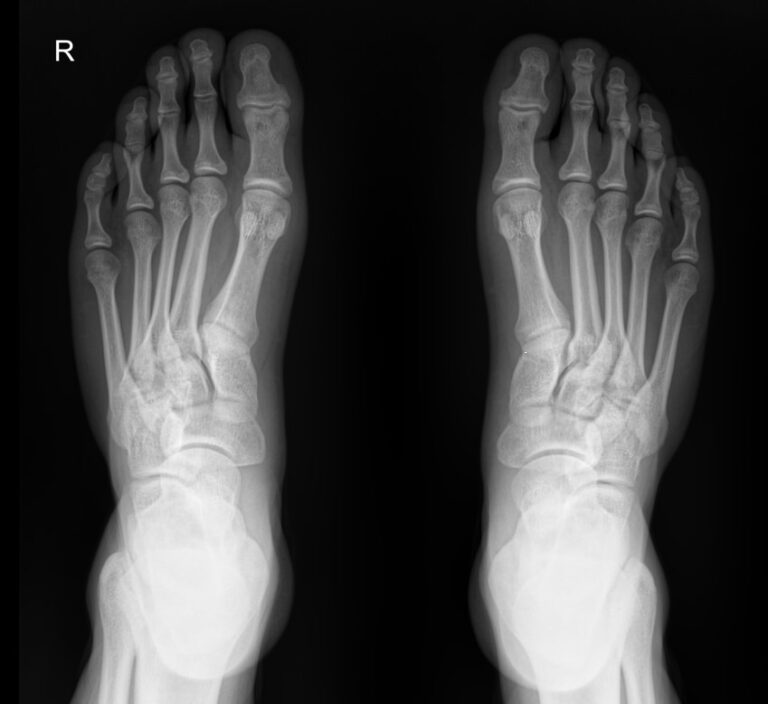

На снимке обеих стоп можно будет сравнить изменения, произошедшие в каждой стопе:

• В состоянии суставных щелей и соответствии суставных поверхностей друг другу;

• В состоянии костной ткани и надкостницы и их целостности;

• В мягких тканях.

Также указываются обнаруженные новообразования, их местоположение.